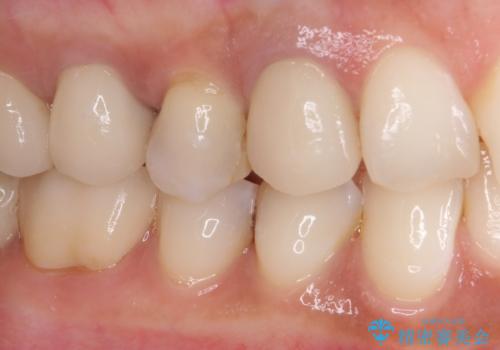

下顎の目立つ位置であるため、セラミックインレーによる修復治療を行うこととしました。

精密に型取りを行ったセラミックインレーを装着したことで、治療後にはしみたり痛んだりという症状は治まりました。